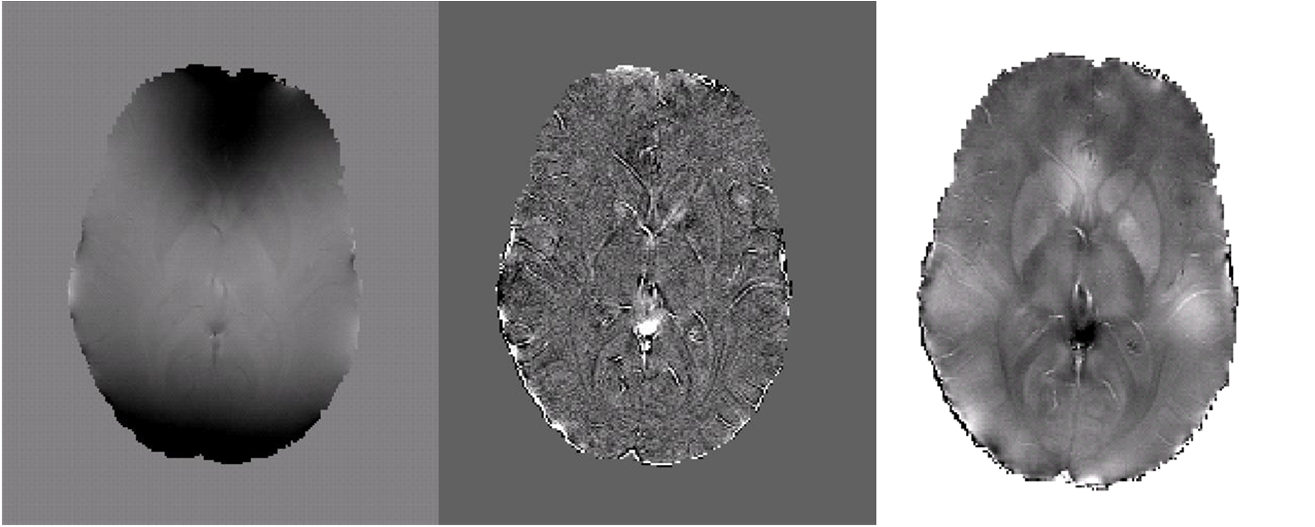

Future work will focus on quantifying magnetic susceptibility and iron content in the brain. Preliminary results based in part on the method described above are shown below in Fig 5.